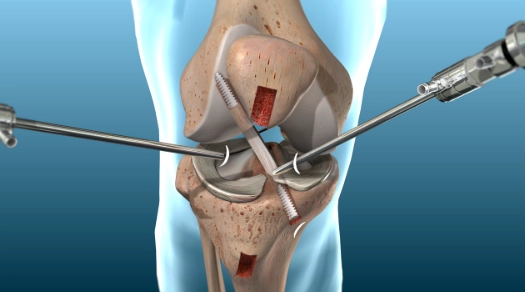

Phẫu thuật dây chằng chéo trước (Anterior cruciate ligament reconstruction)